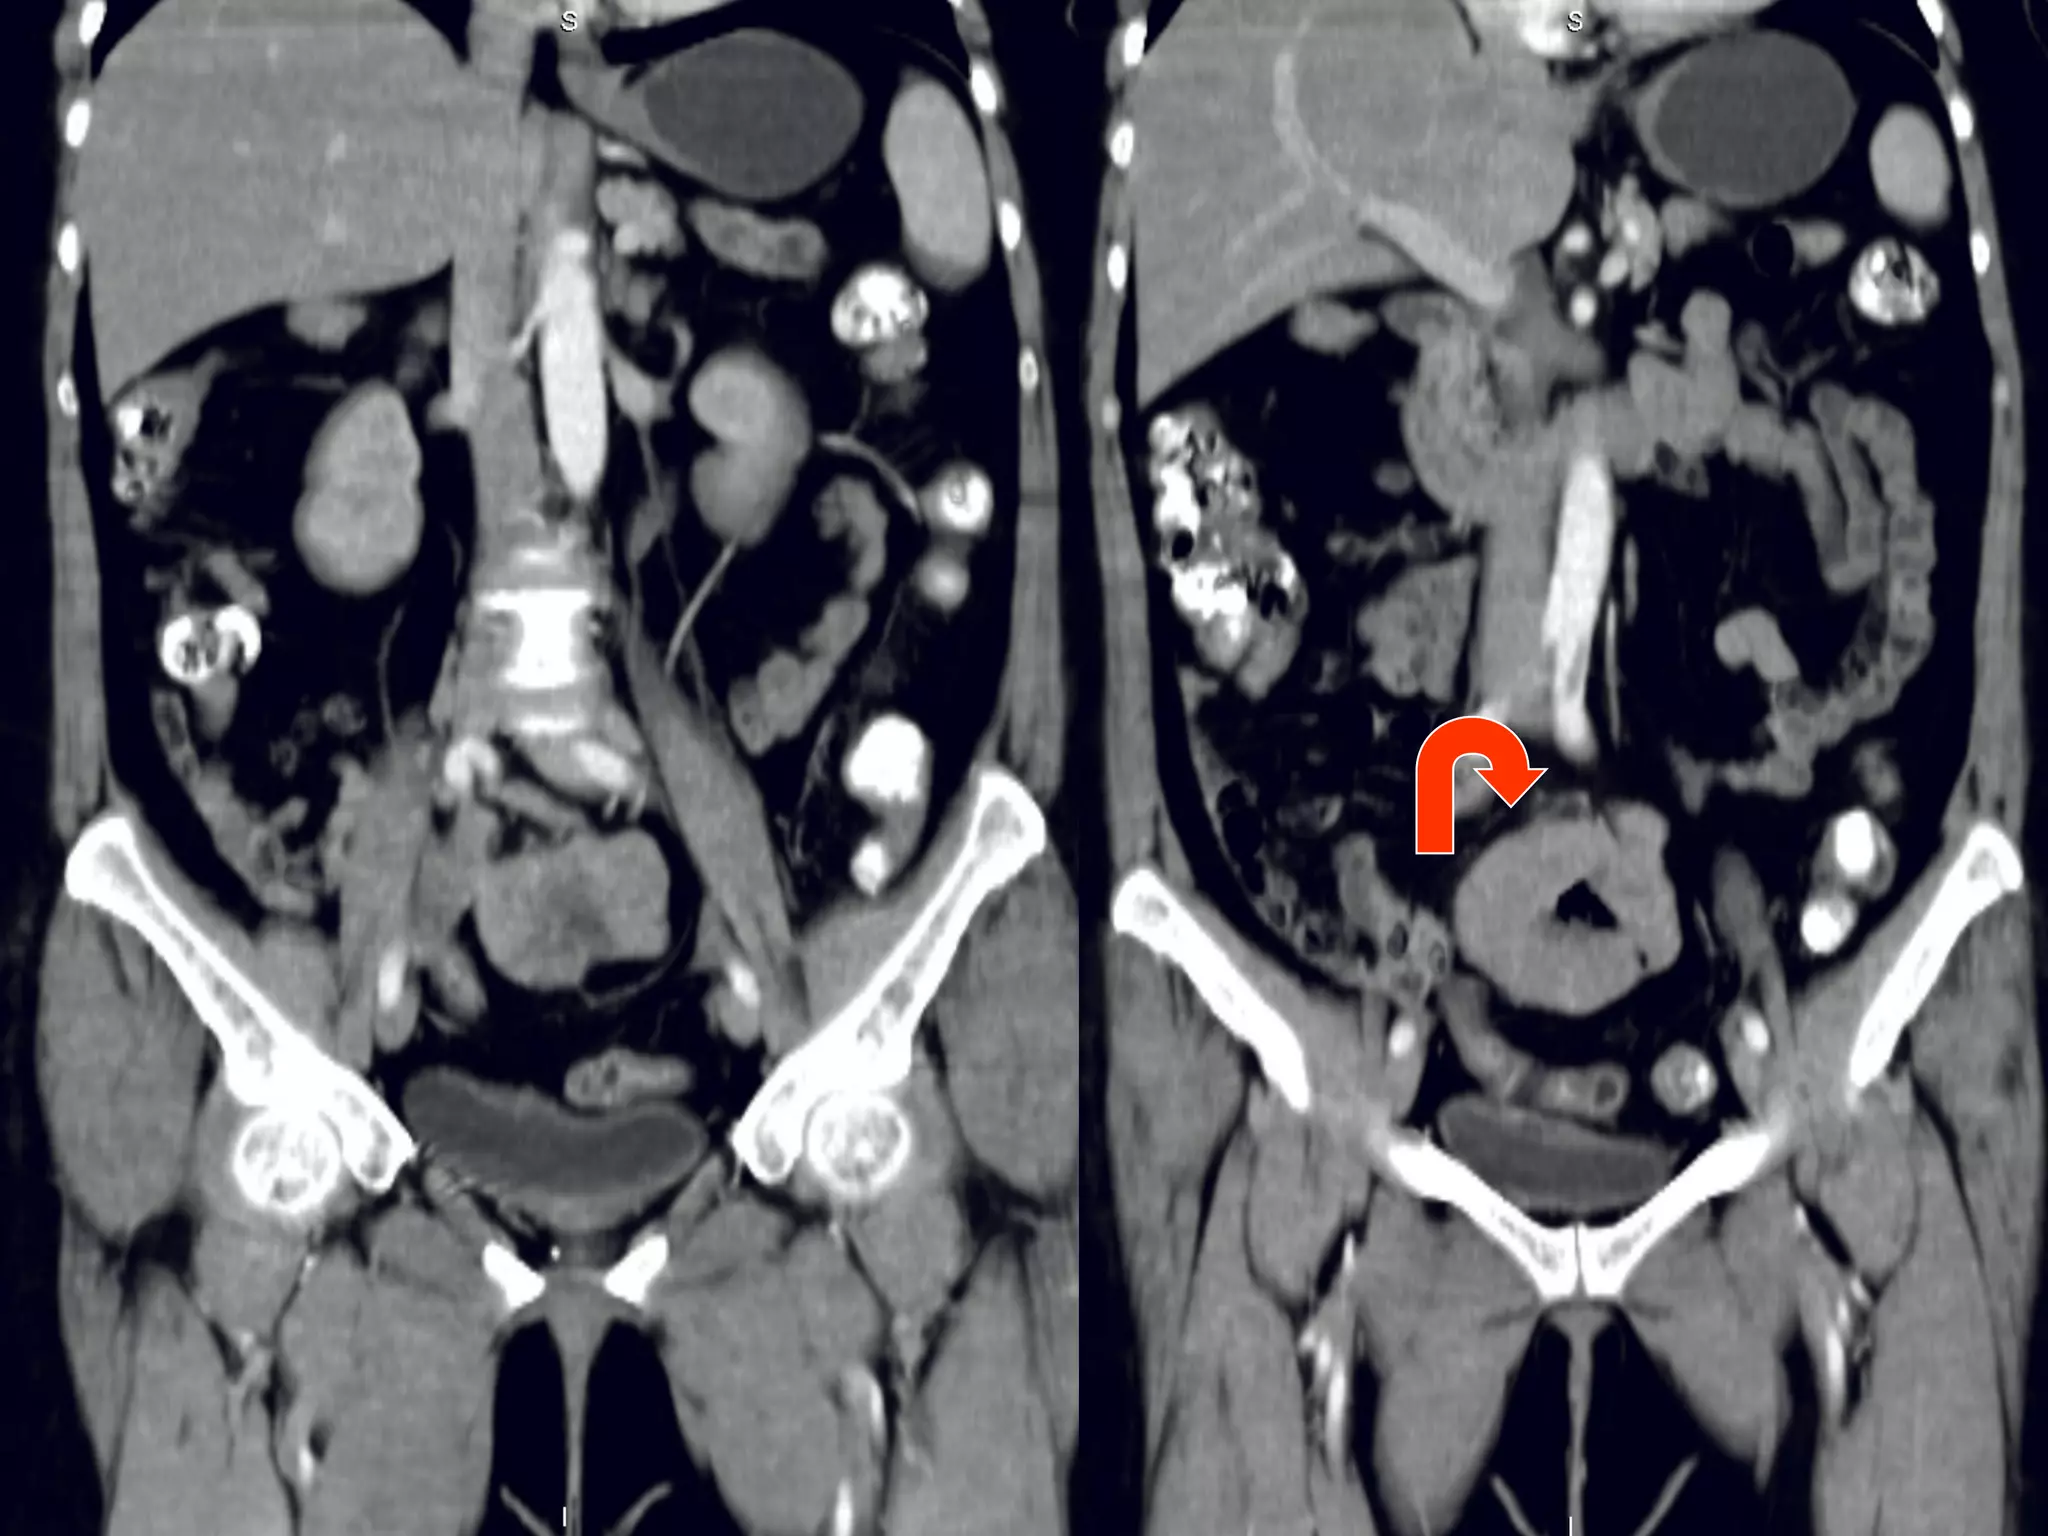

Случай 1. - женщина, 60 лет, госпитализирована в отделение сосудистой хирургии с диагнозом острый тромбоз левой бедренной артерии при скриннинговом УЗИ брюшной полости над мочевым пузырем обнаружено опухолевидное образование  из анамнеза – жалобы на боли в левой ноге, абдоминальных болей, нарушений частоты или консистенции стула не предъявляет при пальпации  объемное эластичное подвижное образование в гипогастральной зоне, чувствительное при глубокой пальпации. В анализах – умеренная гипохромная анемия. Гинекологический статус – без патологических находок. Ирригография– без патологических находок.

КТ-находки Образование с признаками экспансивного роста Локализация -  интраперитонеально инфрамезентериально по срединной линии  По строению напоминает кишечную трубку с циркулярным утолщением стенок, прослеживается их слоистость, просвет выполнен воздухом и жидкостью, четкие контуры Органная принадлежность – подвздошная кишка/ брыжейка, однако не видно типично «входящей» и «отходящей» петли, скорее прилежит к протитво-брыжеечному краю Гомогенно усиливается без признаков гиперваскулярности, внутренний «слой» гиподенсный Нет признаков кишечной обструкции, реакции перифокального жира, лимфаденопатии, подвздошые сосуды не компрессированы, печень не поражена Пристеночный линейный тромб на уровне устья  общей подвздошной артерии слева

Вопросы для дискуссии Сообщение с просветом кишки - следствие некроза или естественный просвет? Почему нет признаков кишечной обструкции? Если опухоль, то какая? Возможно ли, что не опухоль, учитывая анатомическую область?

Gastrointestinal stromal tumor  ( GIST )? Гастроинтестинальные стромальные опухоли (GIST-Gastrointestinal Stromal Tumors) составляют от 0,1% до 3% от всех злокачественных новообразований желудочно-кишечного тракта Типичной локализацией GIST является желудок (60-70%), тонкая кишка (25-35%), толстая и прямая кишка (5%).  Возраст 50-70 лет Часто асимптоматичные, случайные находки, если есть симптомы – обычно это боли в животе, изъязвление, кровотечения и их осложенения.  Просвет обычно не стенозирован, поскольку длительно сохраняется эластичность кишечной трубки, в отличии от карцином обычно медленный рост, метастазируют в печень и по брыжейке Показано иммуногистохимическое исследование

Дивертикул Меккеля? конгенитальная патология,  представляет собой остаток желточного (омфаломезенетриального) протока. Частота 2—3%. Располагается на противо-брыжеечном крае подвздошной кишки в 60— 100 см от илеоцекального угла. Это истинный дивертикул, в его стенке находятся все слои кишки; могут быть и эктопированная ткань желудка, поджелудочной железы, островки толстокишечного эпителия. Обычно асимптоматичен, может осложнятся: перекрут, кишечная обструкция дивертикулит, изъязвление, кровоточение, перфорация грыжа опухолевое поражение